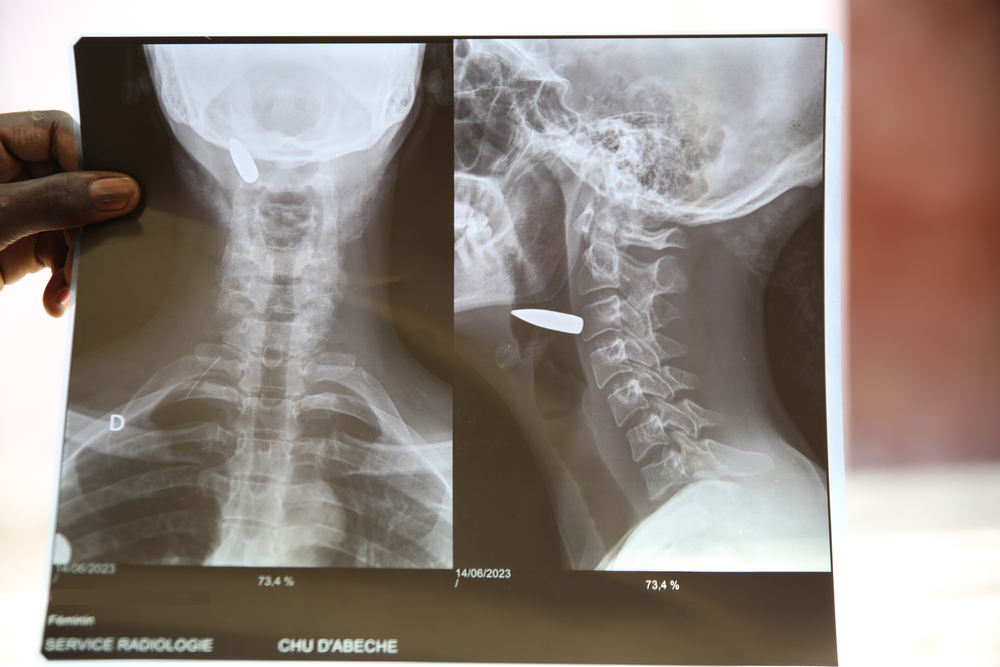

Una mujer recibió un disparo en el cuello en Sudán antes de llegar a Adré, en Chad. Ahí médicos del equipo de MSF la operaron para extraer la bala y sobrevivió en el hospital de Abéché.

Esta foto de la radiografía fue tomada en junio de 2023.